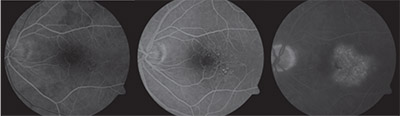

| Figure 2. Optical coherence tomography shows normal foveal contour and retinal architecture in the right eye and retinal edema with intraretinal fluid and attenuation of the ellipsoid zone temporally in the left eye. |

Optical coherence tomography showed normal foveal contour and retinal architecture in the right eye. OCT in the left eye showed loss of the foveal contour, intraretinal fluid centrally and temporally, attenuation of the ellipsoid zone temporally and dilated vascular walls (Figure 2).

Fluorescein angiography with transit of the left eye showed normal transit time and vascular filling, but demonstrated dilated, telangiectatic and aneurismal vessels temporal to the foveal center. Slow petalloid leakage around and temporal to the fovea in late frames was also noted. FA of the right eye showed a normal filling pattern without leakage or vascular abnormalities (Figure 3).

| Figure 3. Fluorescein angiography with transit of the left eye shows dilated, telangiectatic and aneurismal vessels temporal to the foveal center with slow petalloid leakage around and temporal to the fovea in late frames. |